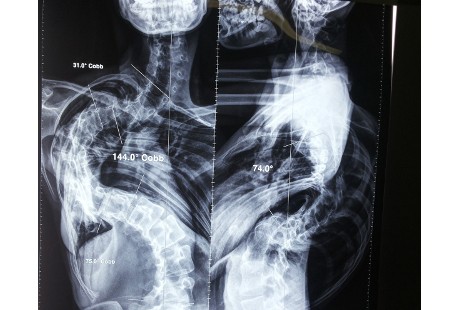

Skoliosis atau tulang belakang yang melengkung bisa disembuhkan dengan ilmu kedokteran. Dwi Setya Wardhani (26) alias Ardha tengah menjalaninya dan mengalami perbaikan, lengkungan yang semula 144 derajat kini menjadi 80 derajat.

Gadis asal Mojokerto Jawa Timur tersebut mengalami skoliosis yang dikategorikan ekstrem. Organ dalam seperti lambung dan paru-parunya sampai kolaps karena terjepit lengkungan tulang belakang. Sungguhpun begitu, operasi telah membuatnya lebih baik.